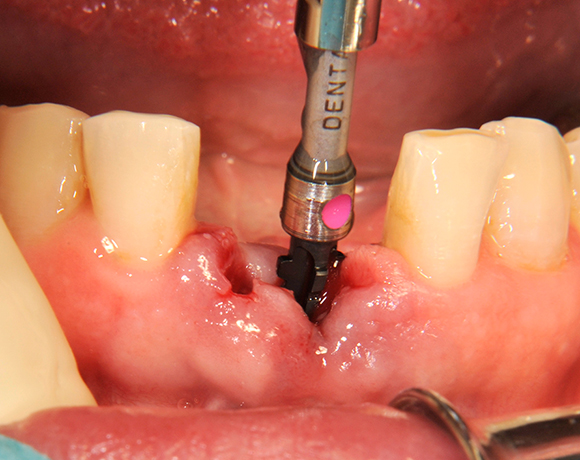

Die Keramikimplantate der Fa. Dentalpoint lassen sich auch zur Sofortimplantation verwenden. Das bedeutet, dass nach Extraktion nicht beherdeter Zähne direkt die Implantate gesetzt werden können.

Im vorliegenden Patientenfall wurden die beiden nicht erhaltungswürdigen, mittleren Unterkieferschneidezähne durch zwei Vollkeramikimlpantate ersetzt.